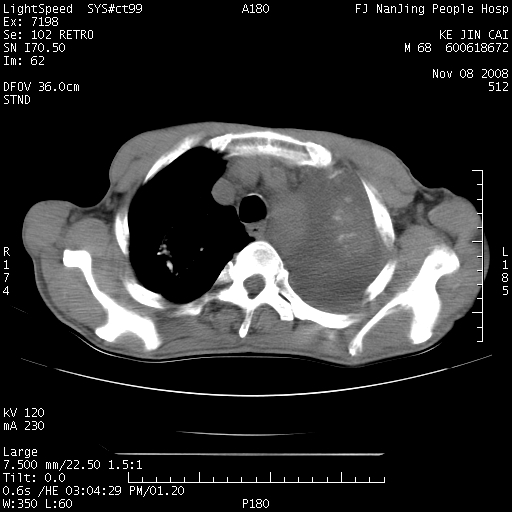

是个很有看头的病例,咋人气那么不旺?没多少人兴趣呢?这个病例几大怪:1   恶性肿瘤侵犯心肌左房怪,心肌一般不会被恶性肿瘤侵犯吧?2   左下肺均匀实变怪,内无含气,有别一般不张实变,含气肺泡完全为液体取代,而非一般不张实变的肺萎陷,冷不丁还以为是肿大的脾脏3   肿瘤本身怪,像tb肺不张4   这么有看头的病例没人气怪。呵呵。

左肺恶性肿瘤侵犯肺动脉,左心房内瘤栓,胸膜转移。

左肺恶性肿瘤侵犯肺动脉,左心房内瘤栓,胸膜转移,少见,学习了。